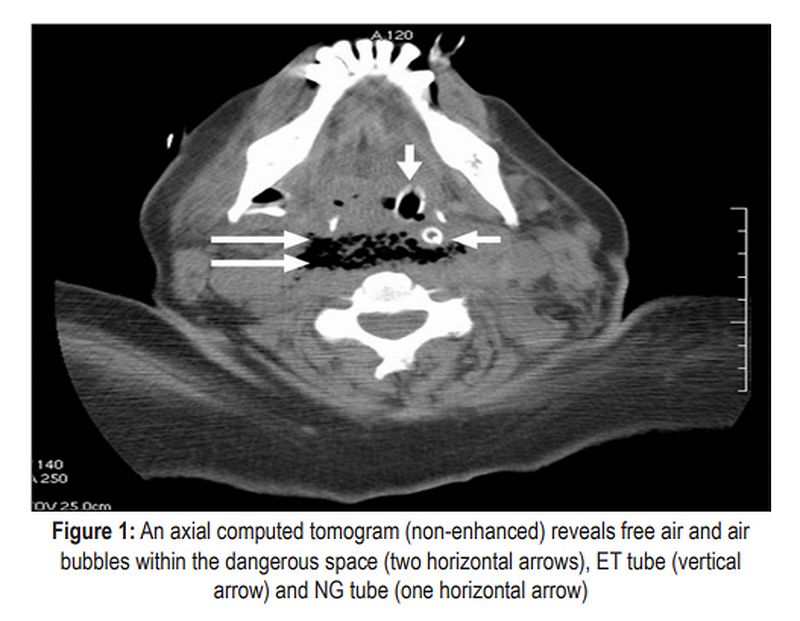

PDF Dangerous space emphysema after dental treatment Dental Surgical Emphysema Treatment Surgical emphysema following dental treatment. Dental treatments leading to emphysema included one case each of crown removal and subgingival curettage, and two. This review provides insight into contemporary prevalence, risk factors and management of surgical emphysema. Cervicofacial subcutaneous emphysema (se) is primarily caused by dental treatment introducing gas into the. Air rapidly dissects into the subcutaneous. Subcutaneous facial emphysema (sfe). Dental Surgical Emphysema Treatment.